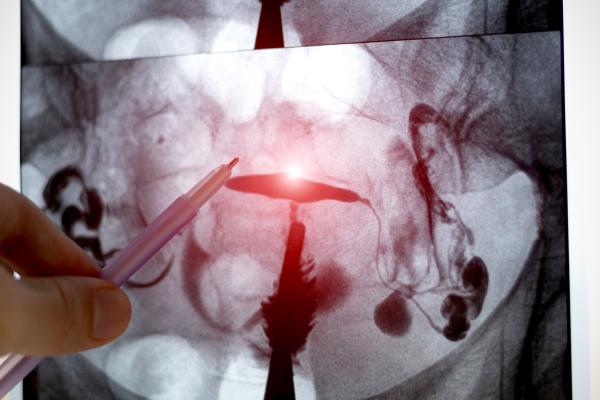

CNNs are computer algorithms that identify specific characteristics in images using a layering technique. This makes CNNs ideal for medical specialties that rely heavily on image-based data—such as radiology and pathology—for interpreting information and making diagnoses. They enable computers to accurately differentiate between, for example, images of cancerous and non-cancerous cells.

At some centres, radiologists already apply machine learning as part of their day-to-day work, including for examining X-rays and CT scans. By comparison, histologists have been peering through microscopes at tissue samples sandwiched between panes of glass since the mid-1800s, which Yip calls the “analog” way of doing things in the new digital frontier.